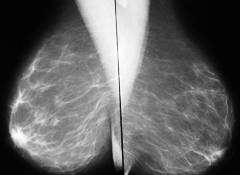

La mamografía se debe practicar en toda mujer a partir de los 40 años y dependiendo de los factores de riesgo debe continuar en controles anuales o bianuales hasta los 50 años a partir del cual debe continuar con examen mamográfico cada año.

DIAGNOSTICO

Se lleva a cabo a través de un proceso que inicia con lo que la paciente refiera de su autoexamen; la información es corroborada durante el examen médico que a su vez se apoyara en exámenes imagenologicos como mamografía o ecografía Según los hallazgos estará indicada la toma de una muestra de tejido mediante una biopsia.